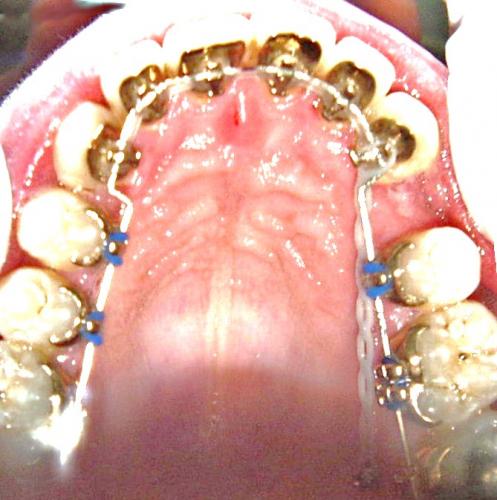

Während der Behandlung

Bild 2: Der Zahnbogen ist schon weiter ausgeformt, die Miniimplantate sind plaziert und der Lückenschluß wird eingeleitet.